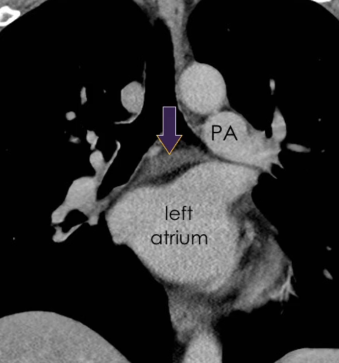

Sinus Transverse

Récessus pulmonaire gauche